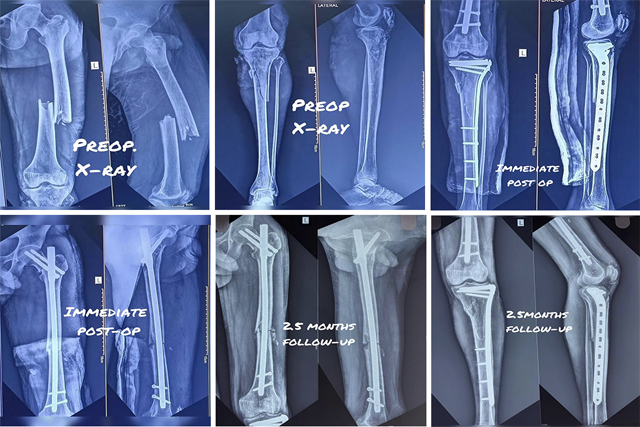

Staged Orthopedic Fixation